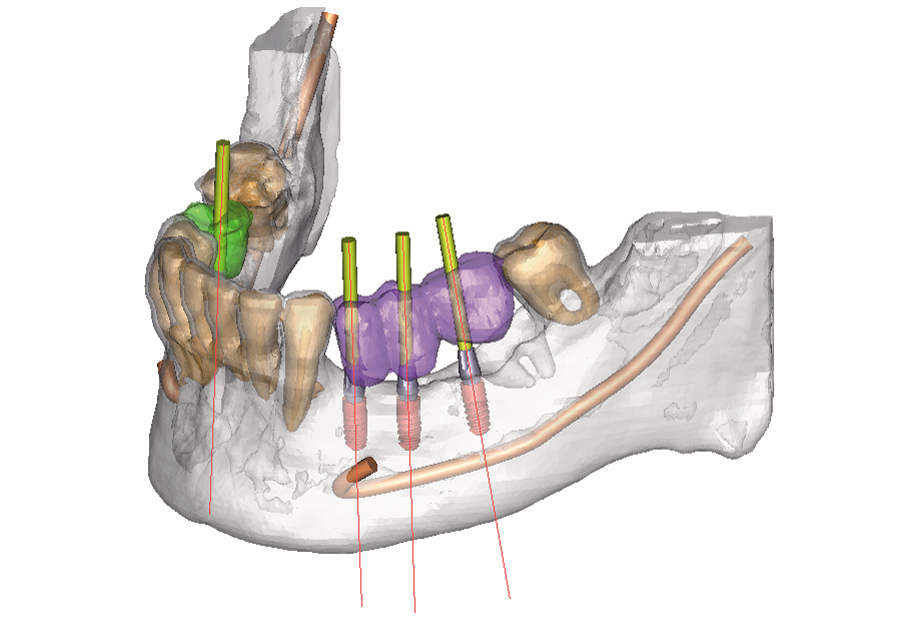

L’intervento si può pianificare attentamente analizzando prima, con la tecnologia radiografica cone-beam a bassa dose radiante, le caratteristiche dell’osso e delle strutture anatomiche e simulando anche al computer il risultato finale.

In questo modo possono essere evitate sedute molto invasive e lunghe per il paziente e se ci sono le condizioni, è possibile avere i denti in bocca già nelle 24 ore successive all’intervento.

In questo modo possono essere evitate sedute molto invasive e lunghe per il paziente e se ci sono le condizioni, è possibile avere i denti in bocca già nelle 24 ore successive all’intervento.